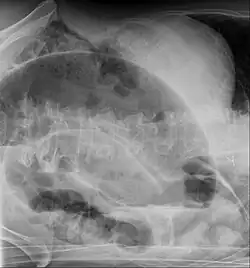

Die Diagnose wird anhand der Klinik und Röntgenaufnahmen des Abdomens (ggf. mit Kontrastmittel), neuerdings auch mittels Ultraschall, gestellt. Die Diagnosefindung insbesondere im Neugeborenenalter kann schwierig sein, da die Klinik lediglich eine Schwellung des Bauches zeigt, und das Röntgenbild unspezifisch sein kann.

Beim Volvulus des Colon sigmoideum findet sich bedingt durch eine massive Überblähung dieses Darmanteils häufig ein so genanntes Kaffeebohnenzeichen (engl. Coffee-bean sign), bei dem eine aufsteigende Schlinge dicht an eine absteigende gelegt ist, so dass sich die Kontur einer übergroßen Kaffeebohne ergibt. Bei bereits stattgehabter Perforation findet sich im Röntgenbild so genannte „freie Luft“.

Bei Erwachsenen wird häufig beim Bild eines akuten Abdomens auch die Computertomographie eingesetzt. Als typisches Zeichen neben der massiven Überblähung beim Volvulus kann hiermit auch die Drehung der Mesenterialwurzel mit ihren Gefäßen (Whirlpool-Zeichen) gezeigt werden.